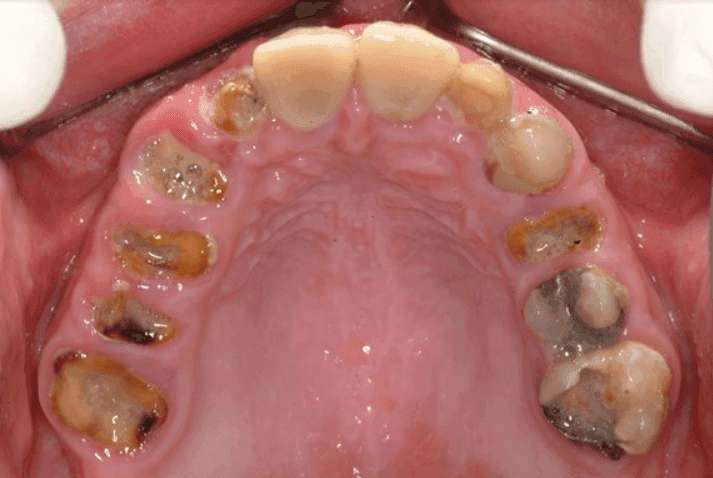

Severely Decayed Tooth

At Smyrna Dental Studio, we understand that dealing with a severely decayed tooth can be both painful and overwhelming. Tooth decay is a common dental issue, but when left untreated, it can progress to severe damage, affecting both your oral health and overall well-being. Fortunately, there are effective treatments available to restore your tooth and relieve discomfort. Let’s explore the causes, symptoms, and best treatment options for severe tooth decay.